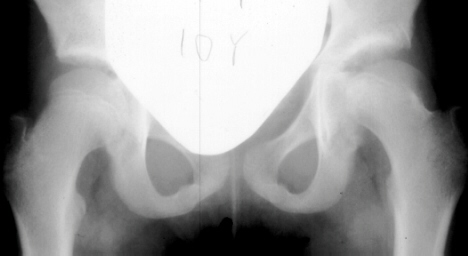

The progression of the hip is documented by x-rays taken at 1 year of age, 2 years of age, 3 years of

age, 5 years of age, 7 years of age, then at ten years of age, early closure of the lateral portion of proximal growth plate observed. Coxa valga was also observed.

The initial changes in the ossific center may follow exactly those seen in Group I, but in addition there is damage to the lateral part of the physis. The early roentgenographic signs indicating lateral physeal damage are: (1) lateral ossification, (2) lateral physeal irregularity and bridging, (3) lateral notching of the epiphysis, and (4) a lateral metaphyseal defect. The damage to the physis may remain dormant. By the age of ten years, however, valgus deformity of the head on the neck develops.( This type occurred in 35% of total AVN at AIDI.)